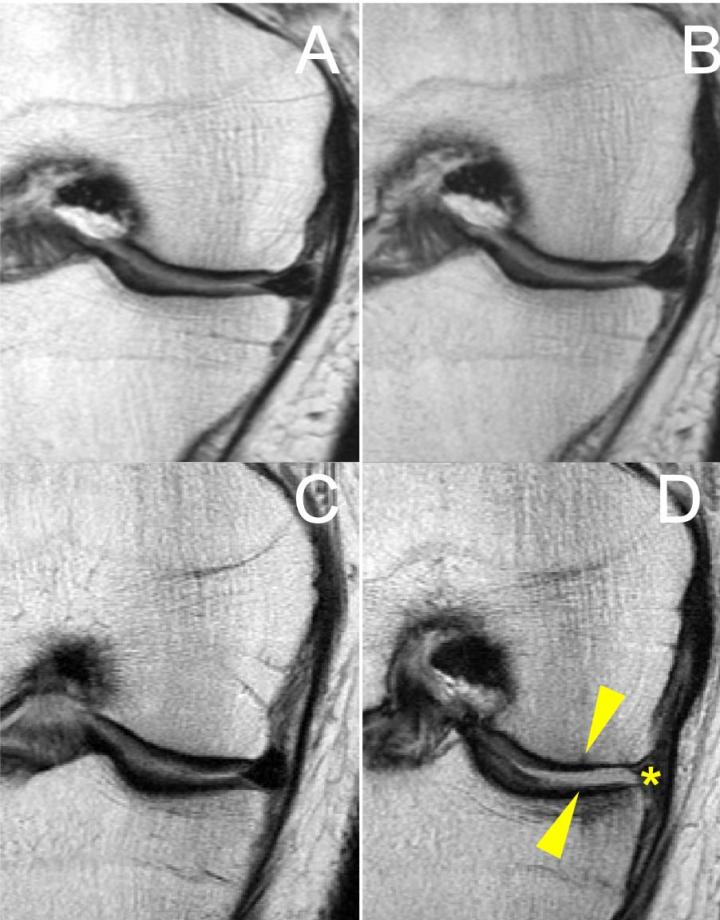

Study participants kept detailed records of their participation in six different types of physical activity, including ball sports, bicycling, jogging/running, elliptical trainer, racket sports and swimming. The researchers performed baseline MRIs and then measured changes in the patients' knees over four years using the modified Whole-Organ Magnetic Resonance Imaging Score (WORMS). A higher score indicates more degeneration.

Patients regularly participating in racket sports saw their overall WORMS score increase significantly, compared to patients regularly using the elliptical trainer over the study period. Surprisingly, the overall WORMS score also increased significantly in the racket sports group compared to the jogging/running group. Racket sports participants saw significantly greater degeneration in the medial tibial cartilage compartment, the compartment on the inside of the knee where arthritis often first appears.

The more rapid degeneration of the knee joints in people who participated in racket sports is likely due to the high-speed lateral movements inherent to such sports, Dr. Schirò said. These movements can affect the femoral-tibia compartment, a structure in the knee made up of the femur condyle, the rounded end of the thighbone that helps it slide over the tibia, or shinbone, and the meniscus, the rubbery, C-shaped cartilage between the thighbone and the shinbone.

"A large lateral force imparted at the foot during side-to-side movements may be driving large knee adduction moments, a key feature in medial compartment disease, which imparts high compressive loads on the medial tibia and femoral condyle," she said. "In support of this premise, the racket sports group showed elevated cartilage degeneration in the medial tibia."

The researchers theorize that joint mechanics are impaired in overweight and obese individuals, with a harmful joint overload triggering increased contact stress on the meniscus. Damage to the meniscus compromises the protective cushion on the cartilage of the knee.